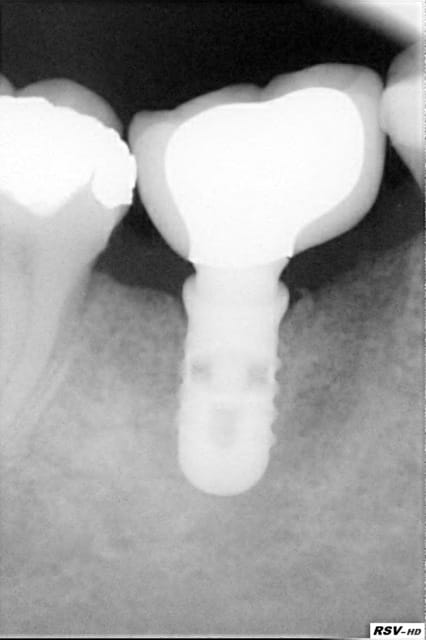

Alors voilà le premier cas :

EII sur 24 du 16/09/10

Obtention d'une stabilité primaire, mais plutôt fragile.

Temporisation par bridge Maryland collé sur une couronne métal en distal, ce qui a été la cause de multiple descellements, et possible traumatismes de l'implant via sa vis de cicat.

Manifestement une autre cause possible est la présence d'une infection maousse en dans le site le jour de la pose...

Qui dit la faute à Tekka ?